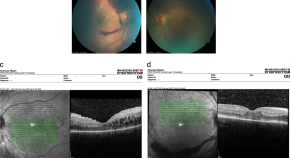

The seminal work of Wennberg and Gittelsohn in 1973 emphasised the importance of health information for informed decision-making. This led to the creation of the Dartmouth Health Atlas in 1996, which has become an important resource for monitoring health services in the USA. The Dartmouth Health Atlas research revealed the existence of variation in health care without benefit to patients, and the dependence of health care use on local resource supply. Similar initiatives emerged around the world, from the UK to Asia. The availability of administrative data has become essential for evaluating health service delivery and for informing health economic analysis and policy decisions. Access to data depends on the organisation of the health system, with more centralised systems facilitating comprehensive data collection. We contrast the decentralised structure of the Swiss healthcare system with that of the US and the UK, and highlight the challenges of harmonising data for nationwide health monitoring. The example of optical coherence tomography (OCT) in Swiss ophthalmology illustrates the variability in care practices and billing patterns. This variability can be attributed to the lack of clear guidelines and the complexity of billing codes. Incentives to charge incorrect rates influence billing, adding a further variance component to the variance in care that cannot be subtracted from the total variance at the level of a health insurance fund and distorting the results. In certain environments the quality of data on care is so variable that a sound conclusions for health policy decisions represent a great challenge.